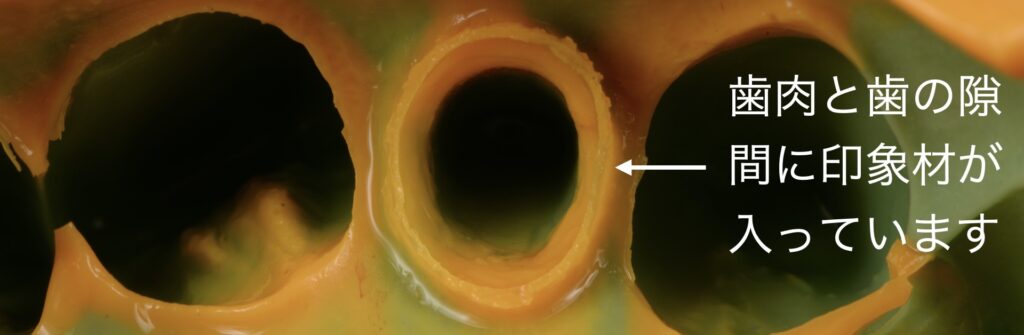

上記のように丁寧に形を整え、歯肉と歯の隙間(歯周ポケット)に糸を本巻きます。

そして、型取りの材料を入れる直前に、その糸を取り去ります。糸の太さ分開いた歯肉と歯の隙間に型取りの材料を流し込んでいくと、型取った際に上記のように歯肉と歯の境目が明瞭に浮き出てきます。

そうすることで、歯と歯肉の境目が模型上に反映され、適合の良い詰め物や被せ物を作製することができます。

この際使用している型取りの材料は、変形量の少ないシリコン性のものを使用しておりますので、材料によるエラーは極力生じないようにしております。